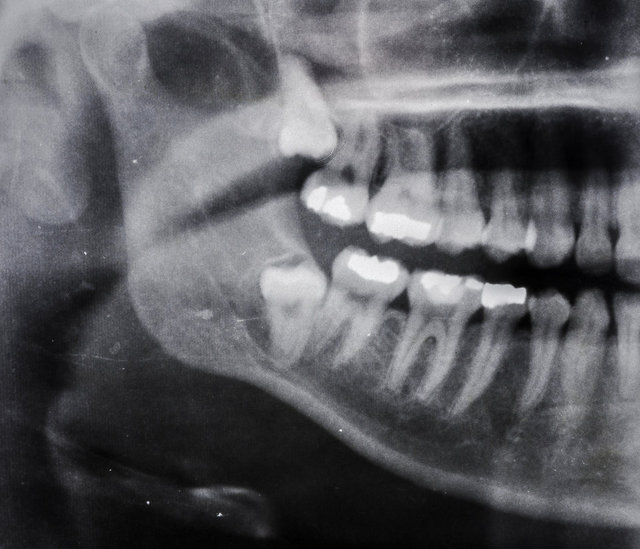

YİRMİLİK YAŞ DİŞ EKSİKLİĞİ

İnsanların tahmini olarak yüzde 5 ila 37’sinde yirmilik diş bulunmaz. Geçmiş zamanlarda yirmilik dişler tüketilen besinleri daha rahat çiğnemek için kullanılıyordu ancak zamanla çene yapısı evirilerek yirmilik diş oluşturmamaya başladı.